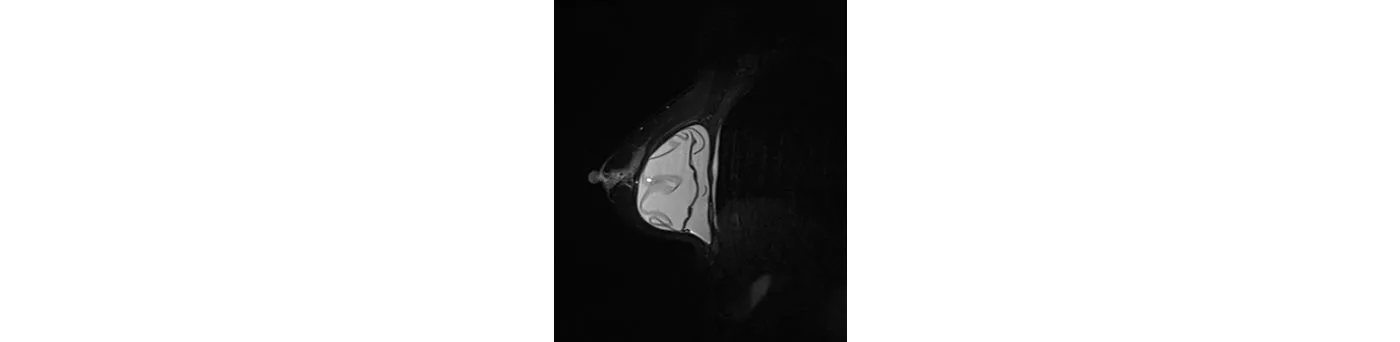

A 51-year-old female patient, 10 years after breast augmentation having regular examination. The MRI diagnosed a completely ruptured implant in the right chest.